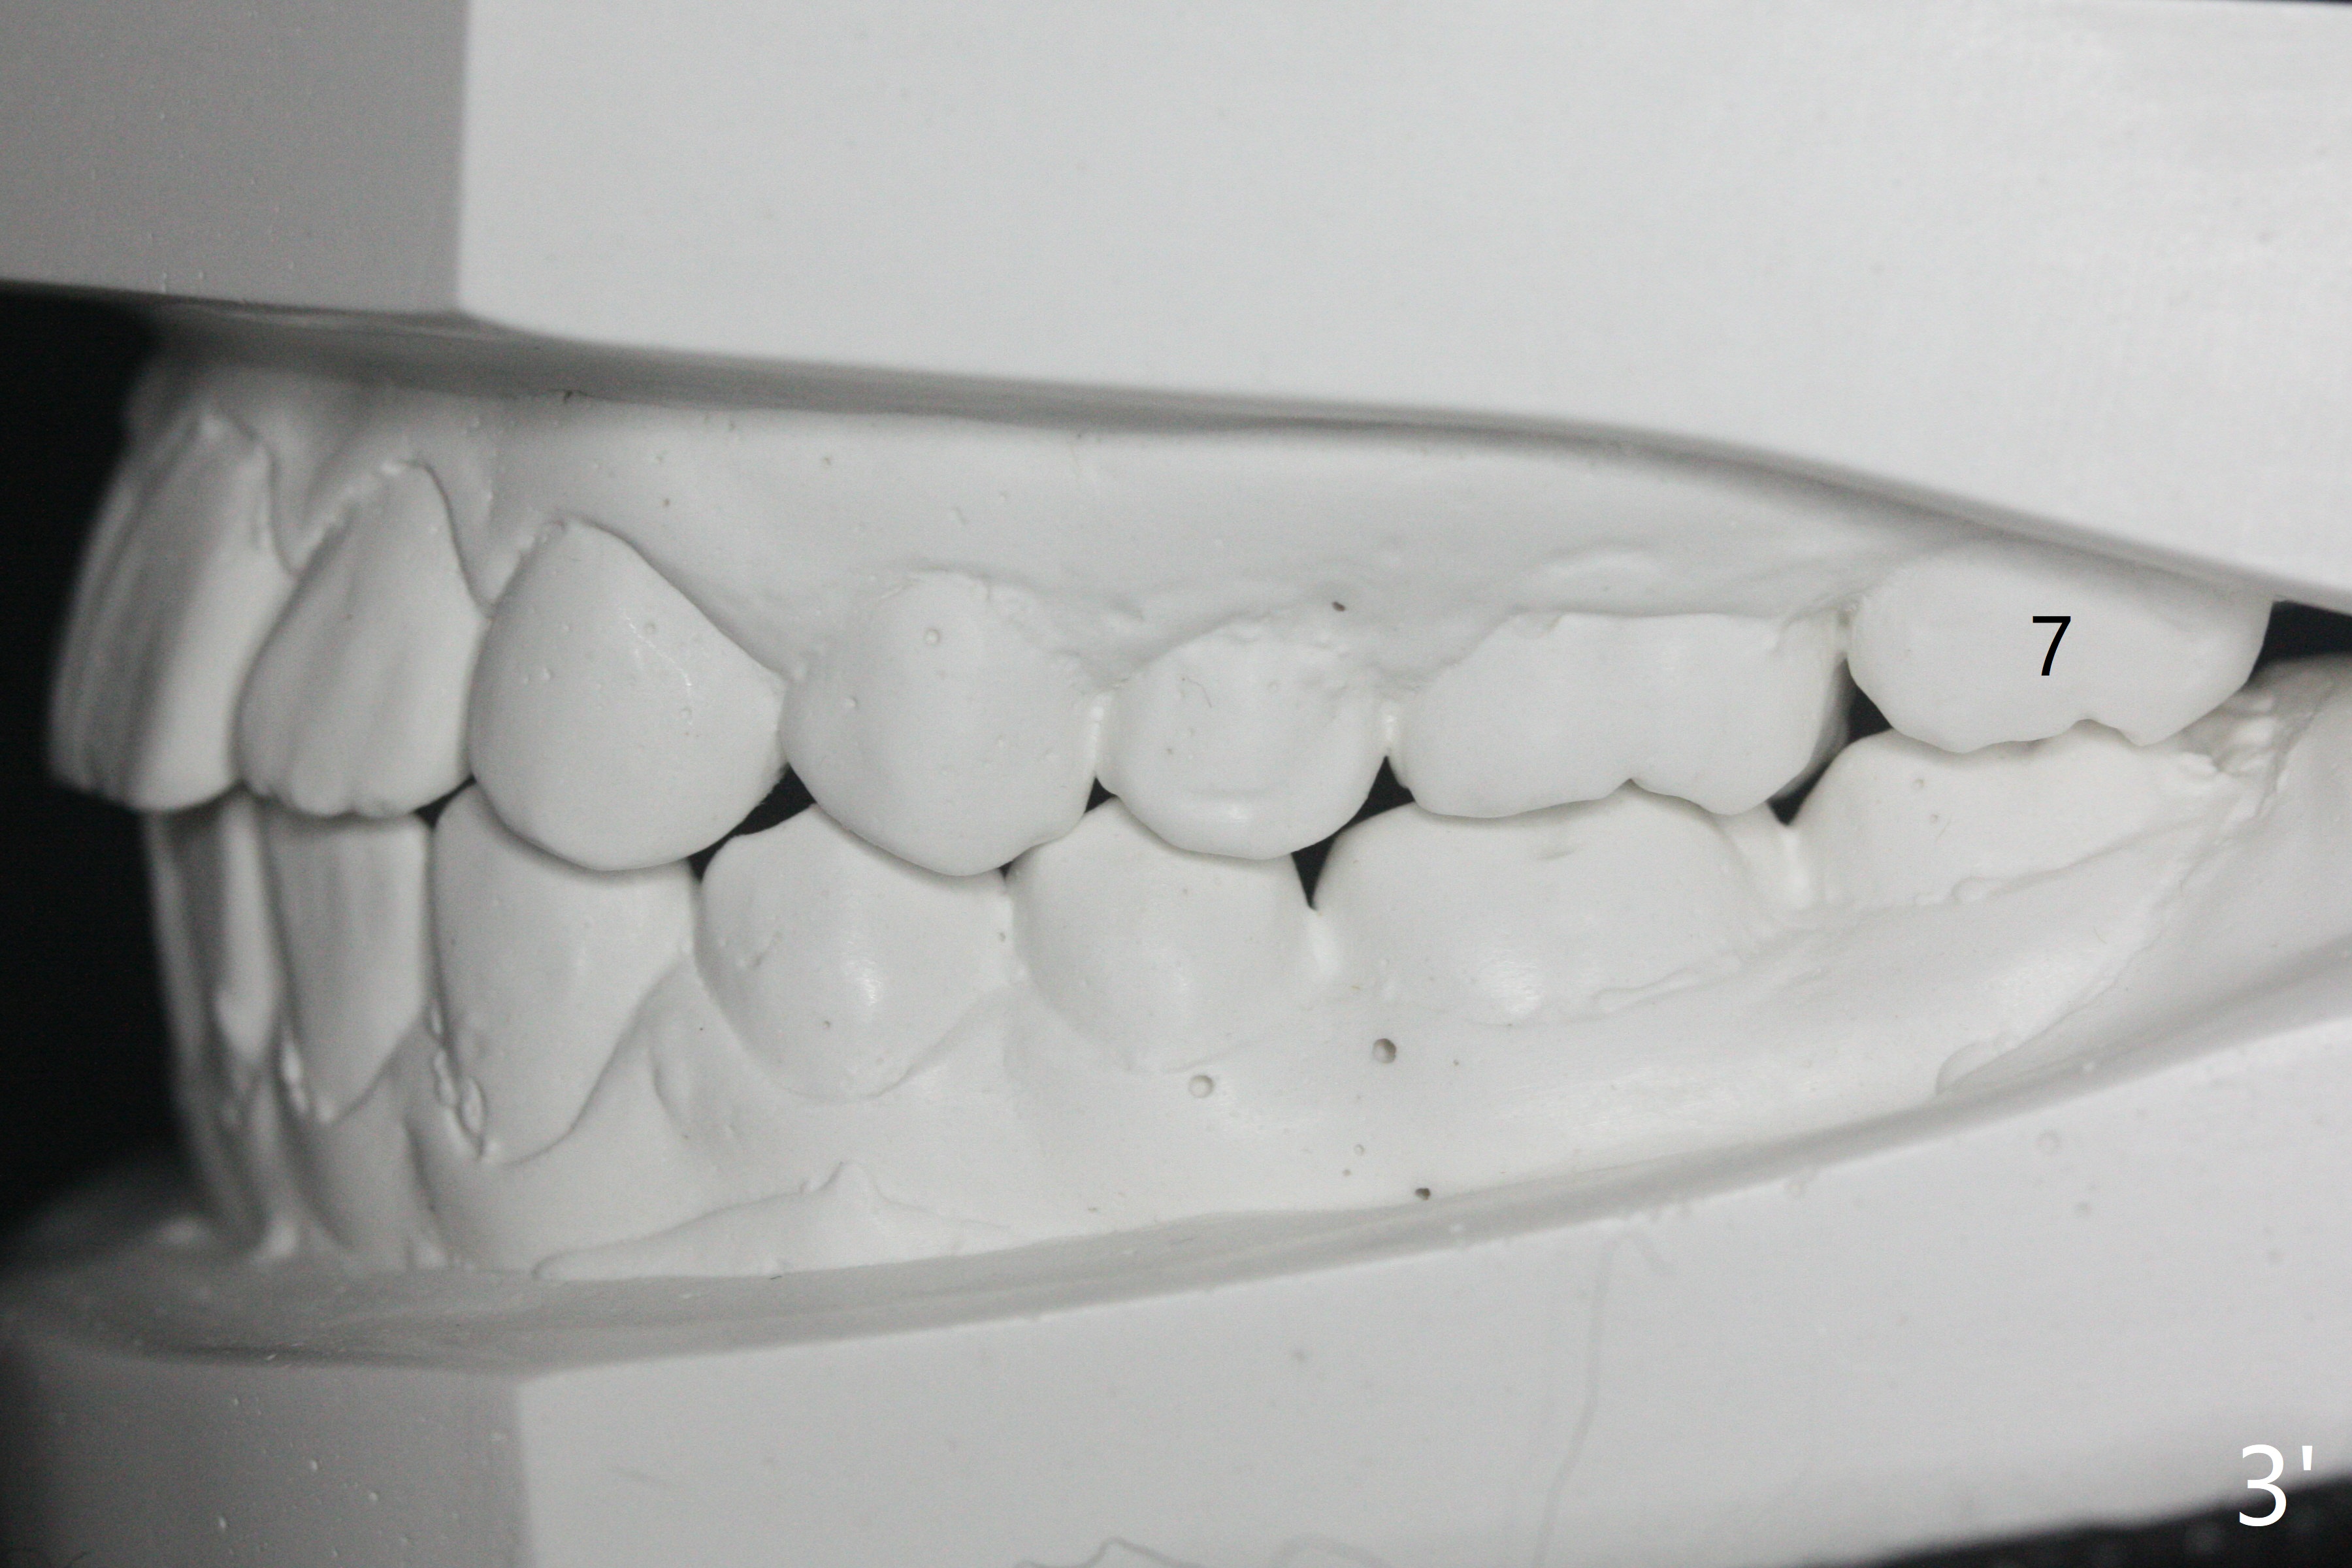

A 12-year-old woman has severe crowding including UL7 impaction (Fig.1-5), finishes non-extraction orthodontics at the age of 15 (Fig.1'-5') and returns for retainer remake at 19 (Fig.1''-5''). Four years post debanding, UL7 (Fig.4') seems to improve its position (Fig.4'').